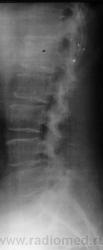

Пол пациента: Женский пол Тип патологии: Сосудистое заболевание Область исследования: Спинной мозг и периферическая нервная система Методы исследования: Rg Женщина поступила в неврологическое отделение с жалобами на онемение нижних конечностей. Сильные боли при повороте туловища, наклоне. https://radiomed.ru/sites/default/files/styles/case_slider_image/public/user/12/2.sl272924-1a.jpg?itok=gqeBvoQ7 ID:5809 Втр, 24/08/2010 - 17:32 #1 Катенёв Валенти... Не на сайте Был на сайте: 7 лет 2 недели назад Зарегистрирован: 22.03.2008 - 22:15 Публикации: 54876 На мой взгляд, при такой комбинации антелистозов, конечно, может быть, и не только "онемение" ног. Приложения: Ср, 25/08/2010 - 23:05 #2 Катенёв Валенти... Не на сайте Был на сайте: 7 лет 2 недели назад Зарегистрирован: 22.03.2008 - 22:15 Публикации: 54876 А. где пациент Игорь Артурович? Чт, 26/08/2010 - 00:25 #3 stroganoff Не на сайте Был на сайте: 15 лет 2 месяцев назад Зарегистрирован: 26.05.2010 - 16:53 Публикации: 57 А еще в Th12 есть крупный задний остеофит.

На мой взгляд, при такой комбинации антелистозов, конечно, может быть, и не только "онемение" ног.

А еще в Th12 есть крупный задний остеофит.